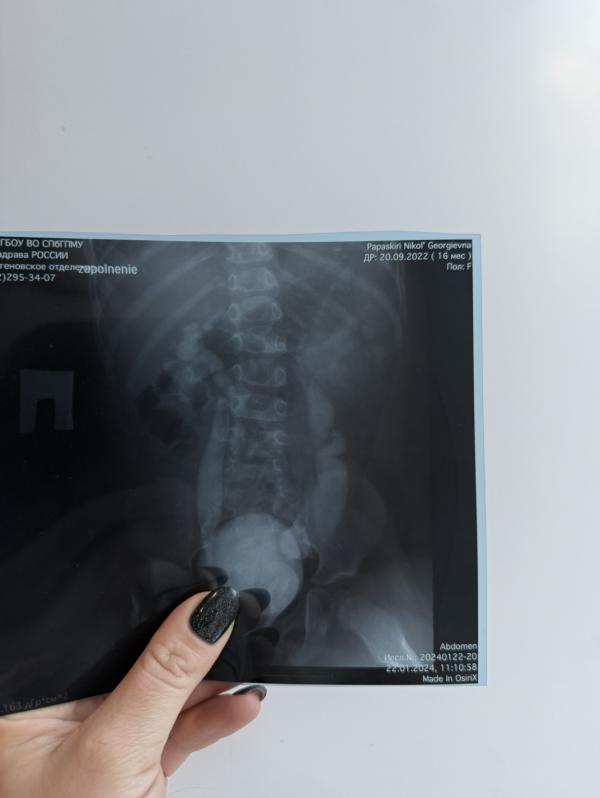

4.снимок это уже сейчас ,чуть видно с одной стороны мочеточник , но он ровный тонкий 🔥и сейчас его вообще не видно ❤️

Работа врача 🔥Ответ от организма Николь 🔥 результат 🔥